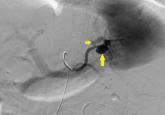

ArticleAnother complication of cirrhosisAuthor:Eyas Alkhalili, MDPublish date: September 1, 2017A patient with cirrhosis presents with acute abdominal pain and shock.Read More